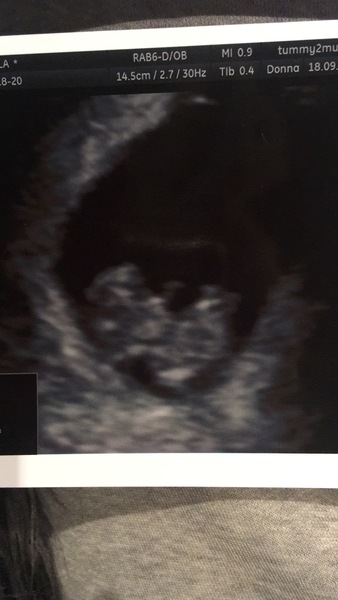

Hi no result back yet, pretty sure it’s just a cold. Feeling better by the day. I’ve had a right scare today though, I started bleeding. First was red discharge, then rusty red, now brown at the moment. Brought my scan forward to this eve and baby is fine. Turns out I have a hematoma outside the uterus, it’s about 1cm big and will hopefully sort itself out but I’m to expect more bleeding especially brown she said. Cervix is closed and baby is measuring 9+1 and arms and legs wriggling, we even got a wave! Sorry if it seems irresponsible to go to scan but I’m pretty confident I don’t have it, it’s more to satisfy school. Also the panic took over xx

@Pugprincess Glad you’re beginning to feel a bit better. Sorry to hear about the bleed, how scary! Glad you managed to move the scan though and that all was ok - and that you know what it is if it happens again. Lovely scan pic, you can really make out the little features already 🥰